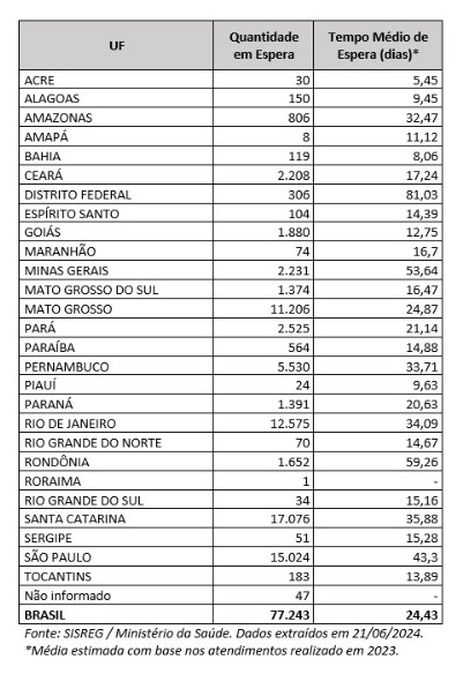

Em junho deste ano, 77.243 brasileiras aguardavam por uma mamografia no Sistema Único de Saúde (SUS). Santa Catarina é o estado com mais mulheres na fila de espera, cerca de 17 mil. Em seguida, aparecem São Paulo (15 mil) e Rio de Janeiro (12,5 mil). Juntos, os três estados somam 56% do total de pacientes à espera do principal exame para detecção do câncer de mama. Os dados foram divulgados nesta quinta-feira (31) pelo Colégio Brasileiro de Radiologia e Diagnóstico por Imagem (CBR).

Segundo a entidade, em alguns locais do país, o tempo de espera por uma mamografia na rede pública pode chegar a 80 dias. O exame, quando realizado em tempo hábil, permite a detecção precoce de alterações mamárias, aumentando as chances de tratamento bem-sucedido e reduzindo a necessidade de intervenções invasivas e onerosas. “Os números revelam parte da sobrecarga no SUS e devem ser levados em conta, especialmente pelos recém-eleitos nas eleições municipais, na formulação e manutenção de políticas de saúde pública”, avaliou o CBR.

Em nota, a entidade alerta que a fila de espera por mamografias no SUS pode ser ainda mais longa do que o indicado oficialmente. “Isso porque o SISREG [Sistema de Regulação] do Ministério da Saúde, plataforma que deveria registrar em uma fila única as demandas por cirurgias eletivas no país, depende de dados fornecidos voluntariamente pelas secretarias de saúde estaduais e municipais.”

“Um exemplo dessa discrepância pode ser observado no Distrito Federal, onde o sistema nacional informa uma fila de espera de 306 pacientes aguardando pelo exame. No entanto, dados divulgados pela imprensa local, baseados no Mapa Social do Ministério Público do Distrito Federal e Territórios (MPTDF), apontam que o número real de mulheres à espera de uma mamografia é dez vezes maior, alcançando 3,6 mil.”

Para o CBR, a disparidade entre regiões e o tempo médio de espera também figuram como preocupações no contexto da realização de mamografias no Brasil. A entidade aponta “necessidade urgente de intervenções eficazes e de políticas públicas capazes de reduzir as filas e garantir acesso equitativo ao diagnóstico”.